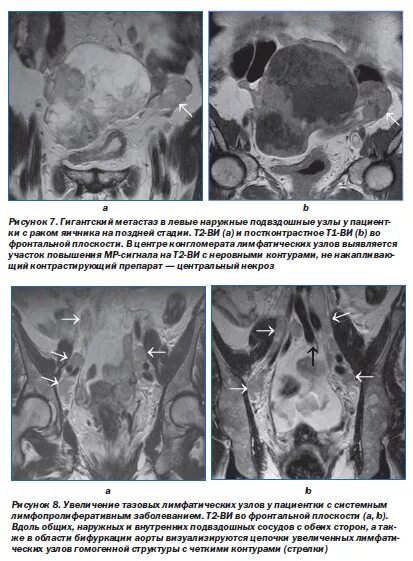

Метастазы после химиотерапии